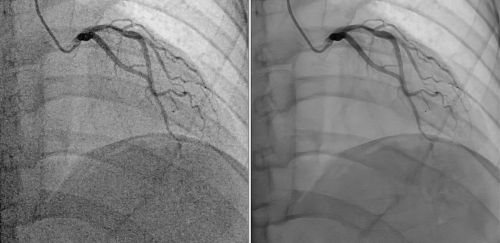

HAN-LINK平台的核心竞争力源于其独创的“智能时空降噪量子态坍缩算法”。该技术通过AI深度学习与量子边缘保护机制,实现了噪声的智能感知与动态消除,将图像信噪比(SNR)和算力提升至行业新高度。其中,依托HAN-LINK平台全新算法,我们在冠脉上实现了全新的冠脉HD4.0版本,该算法采用AI训练的自适应降噪模型,能精准识别并去除噪声,提升影像质量,即使在微剂量模式下,也能提供高清的影像信息,平台可降低80%以上的射线剂量和58%的造影剂用量,同时减少2.7吨铅当量防护废物,在保证影像质量的同时,积极响应全球低碳医疗趋势。

东软医疗HAN-LINK平台以“Human-Centered Design”为理念,深度融合AI技术与临床需求,覆盖心脏介入、神经介入、肿瘤介入等五大领域。其高级临床功能模块包括量子DSA、智能语音助手、卓影多模态影像融合、血管全循环彩色影像等,大幅提升手术效率。例如,在神经介入中,平台可实时生成缺血半暗带量化分析,辅助医生在黄金时间内完成决策;在心脏介入中,AI自动分割血管与狭窄测量功能,为支架选型提供精准依据。